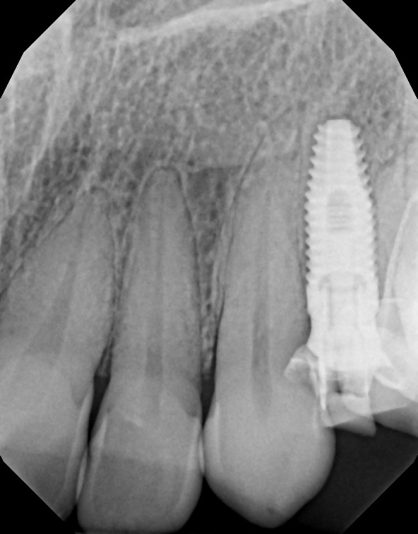

Hey guy, I’m still pretty new to implants. I’ve placed about 30. Looking for suggestions to improve. This is my most recent one. I chose 9 mm implant due to the proximity to the nerve. My main goal was to engage natural bone beyond the apex of the socket without getting too close to the nerve. I used the Densah burs, mostly in OD mode. and…